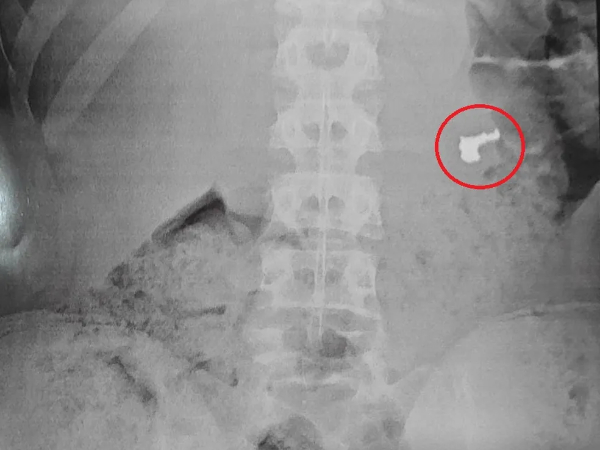

Imagem de Raio-x revela joia no estômago de jovem | Foto: Divulgação

Um adolescente, cuja idade não foi divulgada, engoliu uma corrente de ouro que havia acabado de roubar em Guarujá, no litoral de São Paulo, para evitar ser apreendido em flagrante pela Guarda Civil Municipal (GCM). No entanto, os agentes o levaram a uma unidade de saúde, onde, após uma radiografia, confirmaram que o objeto estava no estômago do suspeito.

Na unidade de saúde, exames de raio-X foram realizados, e o resultado de um deles identificou a joia roubada. Os três menores foram encaminhados à Delegacia Sede de Guarujá, onde a ocorrência foi registrada.